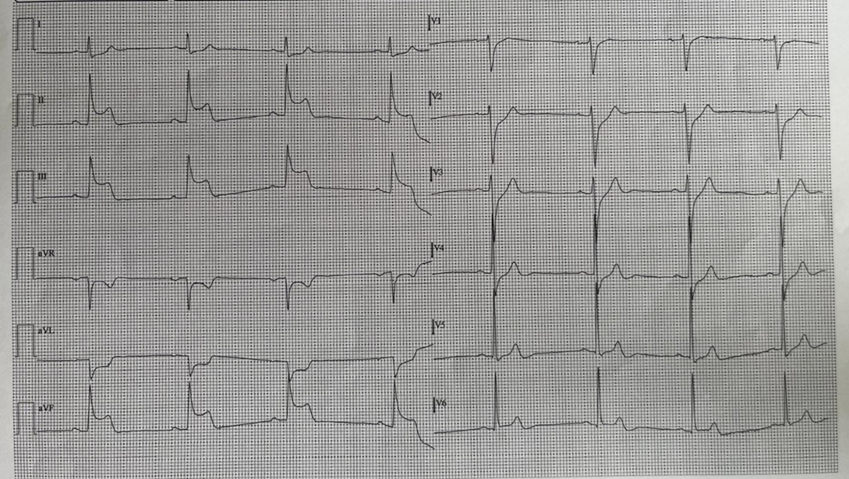

We present the case of a 56-year-old patient, affected by arterial hypertension and with no cardiac history, who called the Emergency number because of an episode of resting angina at home. When emergency vehicles arrive the patient was initially asymptomatic and electrocardiogram was normal. For recurrence of chest pain, a second ECG tracing was performed and it highlighted a second degree atrio-ventricular block, Mobitz 2, ST-segment elevation in the infero-lateral and sub-ST segment in leads V1-V2 (Figure. 1). The patient was then taken to the Hemodynamics of our Hospital for urgent coronary angiography. The exam did not find significant coronary atherosclerosis affecting the epicardial coronary arteries (only a 30-40% stenosis of the right coronary artery in the middle section was described). At the transthoracic echocardiogram performed in the Coronary Unit, significant valvular defects were excluded, the left ventricular ejection fraction (LVEF) was preserved with only a mild hypokinesia of the inferior-posterior wall. In the suspicion of vasospastic angina on the documented atherosclerotic plaque of the right coronary artery, Diltiazem i.v. was introduced into therapy and then orally. In the following 48 hours the patient experienced two different episodes of angina with an ECG tracing compatible with inferior-STEMI and third degree atrioventricular block (Figure. 2). The symptoms rapidly reduced after intravenous nitroglycerin administration, with prompt restoration of sinus rhythm (Figure. 3). Enzyme curve was not significant (hs-TnT 10 ng/L, Ck-Mb 3.4 mcg/L). During the hospitalization the therapy with calcium channel blocker was up-titrated and nitrate was also introduced, without further anginal episodes or major brady-arrhythmias. Considering the mild coronarosclerosis and the high lipoprotein-A levels (Lp(a) 85 mg/dl), we decided to maintain the therapy with acetylsalicylic acid and the Rosuvastatin/Ezetimibe combination. After 5 days the patient was transferred, asymptomatic and with good haemodinamic status, to a cardiac rehabilitation facility. At the follow-up visit in the Day Hospital Ambulatory, 3 months later, the echocardiogram was normal, and the drug therapy was well tolerated. No new arrhythmic events were detected at the control Holter ECG.

Figure. 2: ECG changes during angina attacks